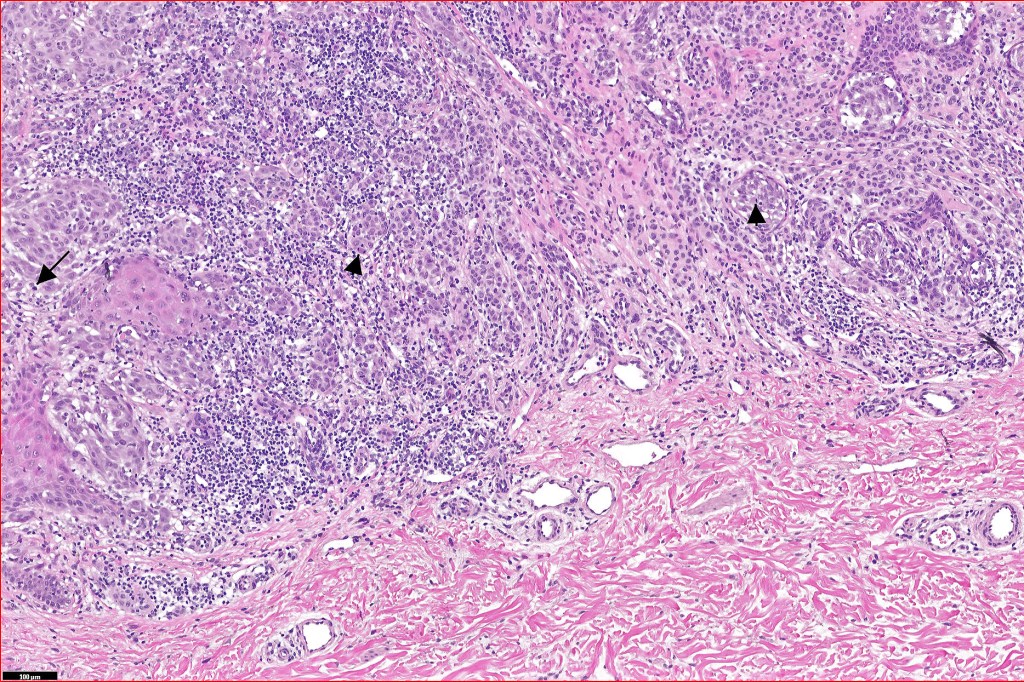

Histological features

•>5-10 mm

•Involve deep dermis or subcutis

•Asymmetrical, poorly circumscribed

•Large nodules which often show impaired maturation

•Loss of gradient with HMB45 and Ki67